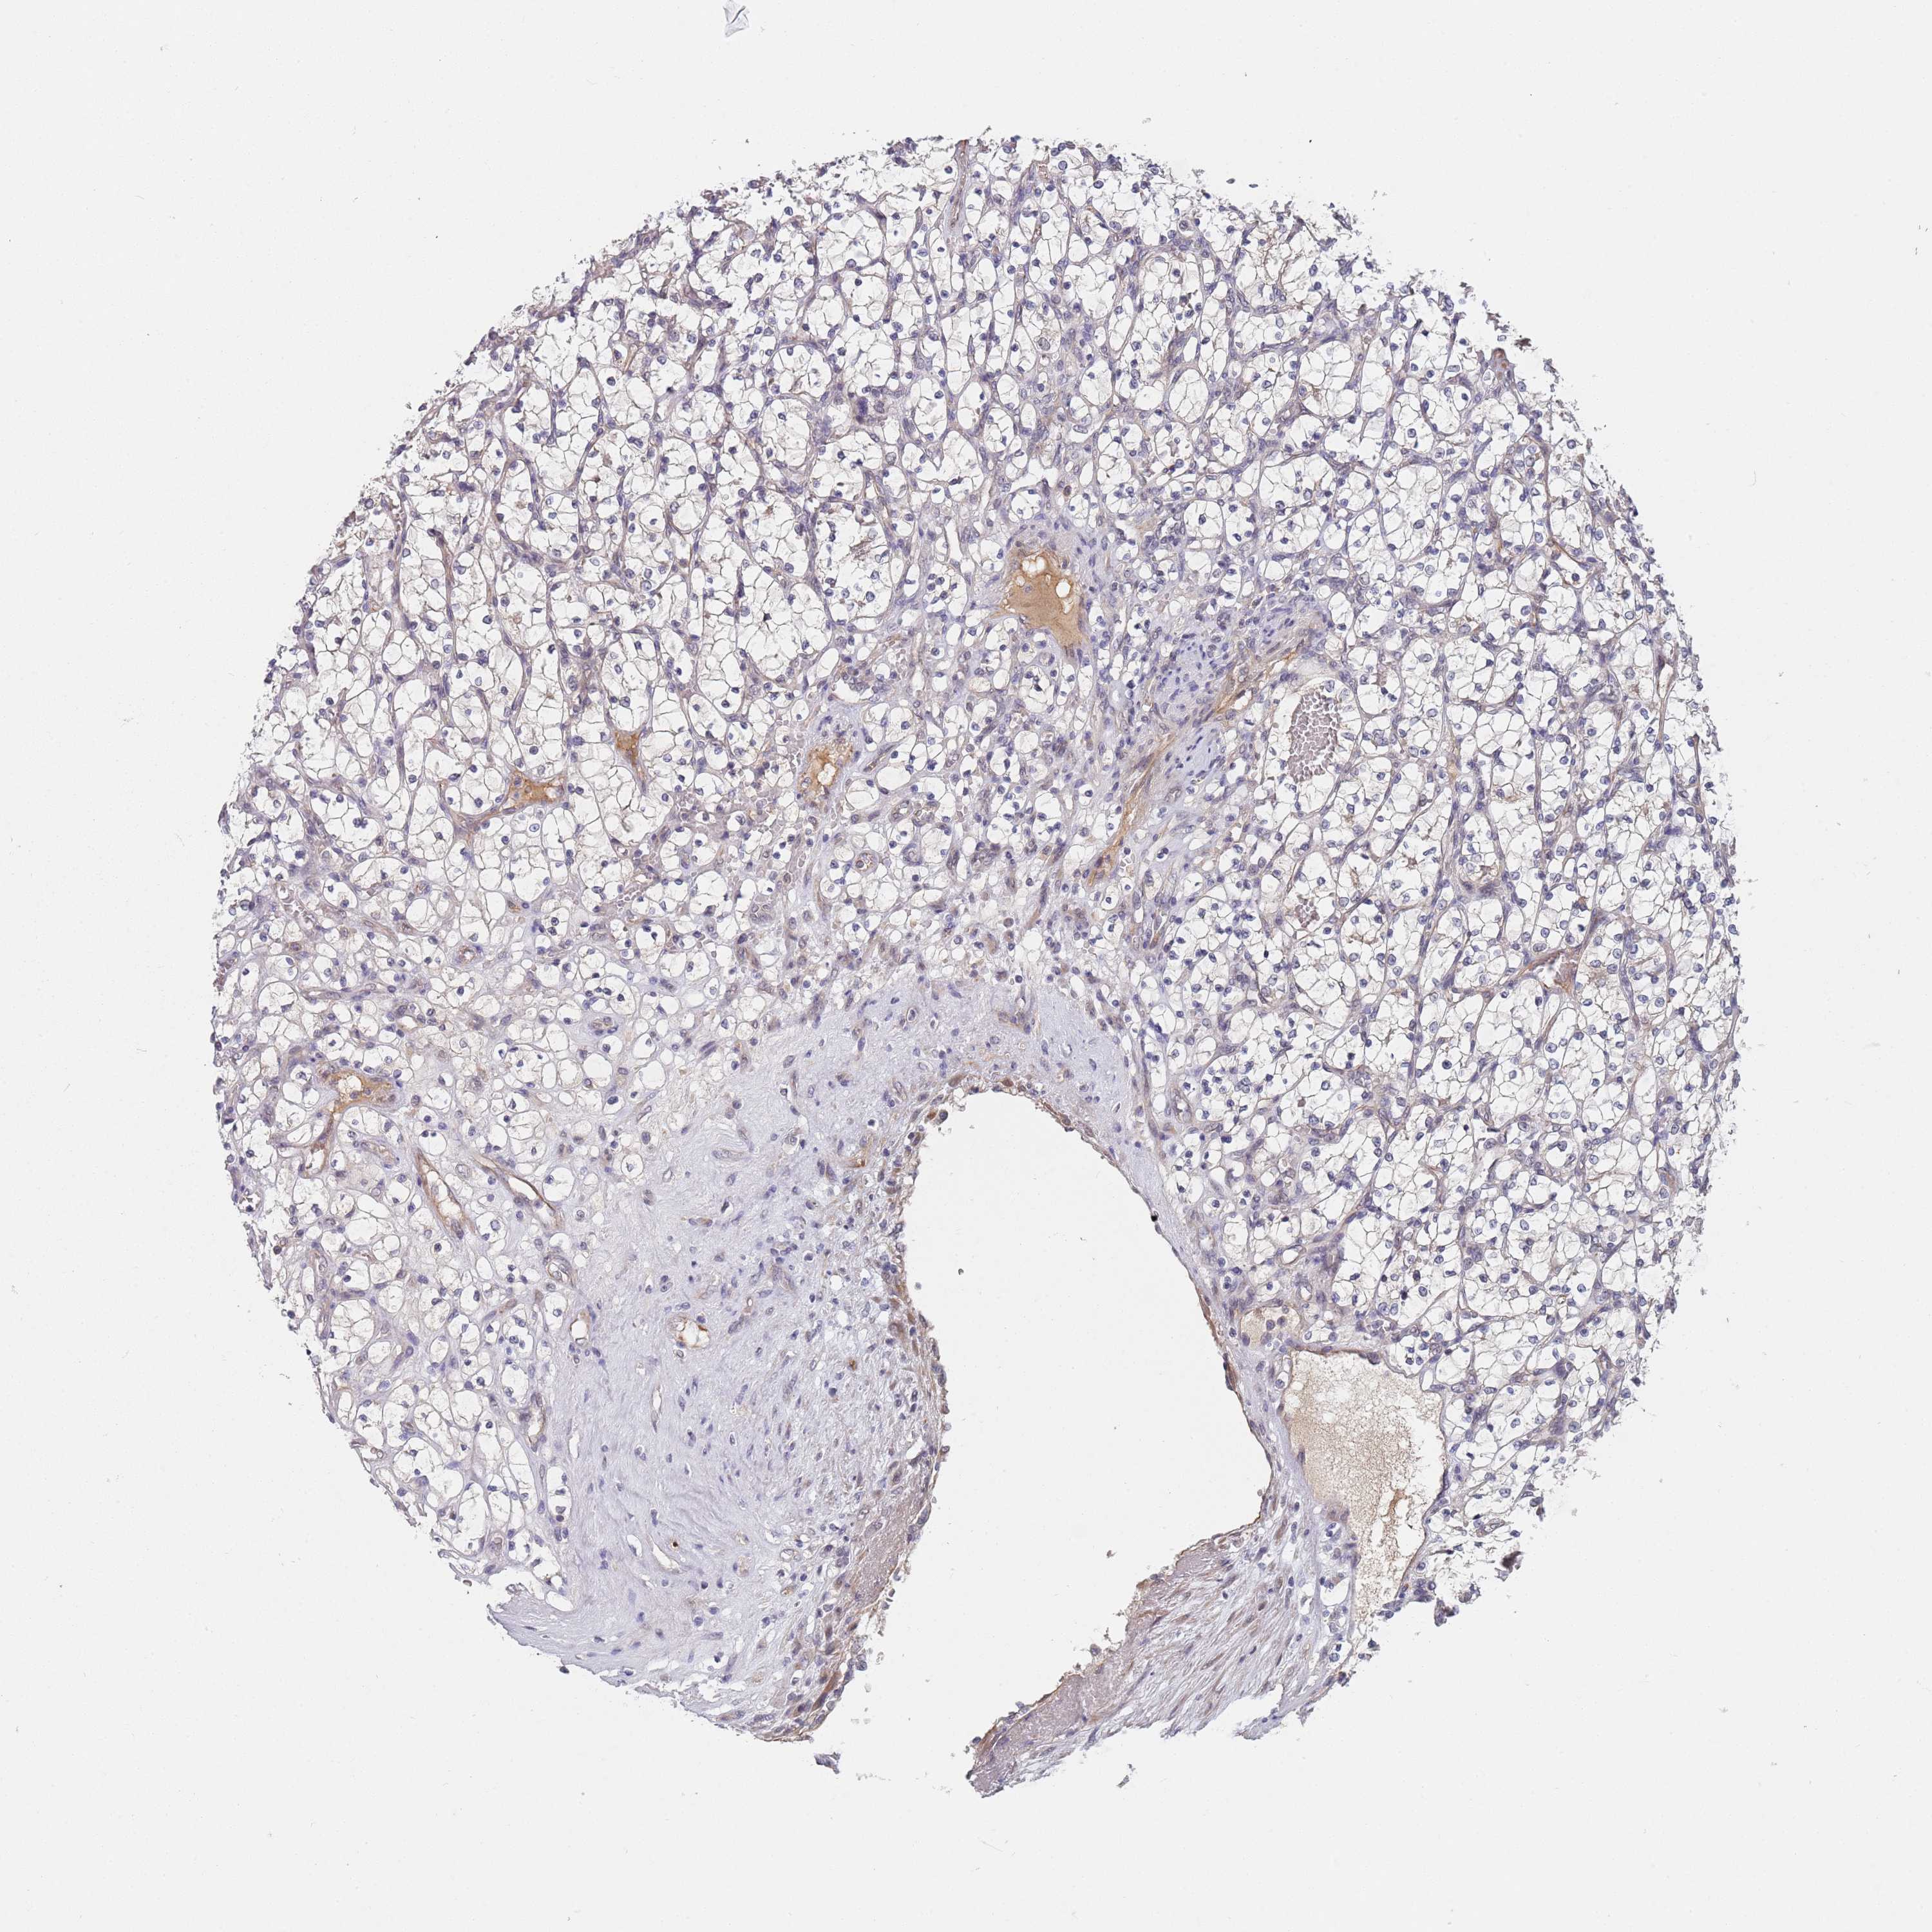

KIDNEY RENAL CLEAR CELL CARCINOMA (VALIDATION) - Interactive survival scatter ploti

The Survival Scatter plot shows the clinical status (i.e. dead or alive) for all individuals in the patient cohort, based on the same data that underlies the corresponding Kaplan-Meier plots. Patients that are alive at last time for follow-up are shown in blue and patients who have died during the study are shown in red.

The x-axis shows the expression levels (FPKM) of the investigated gene in the tumor tissue at the time of diagnosis. The y-axis shows the follow-up time after diagnosis (years). Both axes are complimented with kernel density curves demonstrating the data density over the axes. The top density plot shows the expression levels (FPKM) distribution among dead (red) and alive patients (blue). The right density plot shows the data density of the survived years of dead patients with high and low expression levels respectively, stratified using the cutoff indicated by the vertical dashed line through the Survival Scatter plot. This cutoff is automatically defined based on the FPKM cutoff that minimizes the p-score. The cutoff can be changed by dragging the vertical line or by entering a cutoff value in the square labeled "Current cut-off".

Under the Survival Scatter plot the p-score landscape (black curve; left axis) is shown together with dead median separation (red curve; right axis). Dead median separation is the difference in median mRNA expression between patients who have died with high and low expression, respectively. It is calculated as follows: median FPKM expression of dead patients with high expression - median FPKM expression of dead patients with low expression. This is intended to aid the user in visually exploring custom cutoffs and the associated p-scores and dead median separation.

Individual patient data is displayed and can be filtered by clicking on one or more of the category buttons on the top of the page. Categories describing expression level and patient information include: high, low, alive, dead, female, male and tumor stages. The scale of the x-axis can be toggled between linear and log-scale by clicking on the "x log" button. Mouse-over function shows TCGA ID, patient information and mRNA expression (FPKM) for each patient.

& Survival analysisi

Kaplan-Meier plots summarize results from analysis of correlation between mRNA expression level and patient survival. Patients were divided based on level of expression into one of the two groups "low" (under cut off) or "high" (over cut off). X-axis shows time for survival (years) and y-axis shows the probability of survival, where 1.0 corresponds to 100 percent.

B4GALT4 is not prognostic in Kidney Renal Clear Cell Carcinoma (validation)

Best expression cut offi

Based on the FPKM value of each gene, patients were classified into two groups and association between prognosis (survival) and gene expression (FPKM) was examined. The best expression cut-off refers the FPKM value that yields maximal difference with regard to survival between the two groups at the lowest log-rank P-value. Best expression cut-off was selected based on survival analysis .

When clicking on this number, the vertical dashed line indicating cut-off, the interactive survival plot, and the Kaplan-Meier curve will be adjusted to show results based on the best expression cut-off.

: 19.92

Median expressioni

Median expression refers to the median FPKM value calculated based on the gene expression (FPKM) data from all patients in this dataset. When clicking on this number, the vertical dashed line indicating cut-off, the interactive survival plot, and the Kaplan-Meier curve will be adjusted to show results based on the median expression.

: N/A

Median follow up timei

Median follow up time refers to the median time (years) after diagnosis with this type of cancer, based on clinical data from all patients in this dataset.

P scorei

Log-rank P value for Kaplan-Meier plot showing results from analysis of correlation between mRNA expression level and patient survival.

N/A

5-year survival highi

5-year survival for patients with higher expression than the expression cutoff.

For melanoma and glioma, 3-year survival is shown.

5-year survival lowi

5-year survival for patients with lower expression than the expression cutoff.

TCGA RNA samplesi

RNA-seq data is reported as average FPKM (number Fragments Per Kilobase of exon per Million reads), generated by the The Cancer Genome Atlas (TCGA) .

Normal distribution across the dataset is visualized with box plots, shown as median and 25th and 75th percentiles. Points are displayed as outliers if they are above or below 1.5 times the interquartile range. FPKM values of the individual samples are presented next to the box plot.

Average pTPM 25.1

Number of samples 100